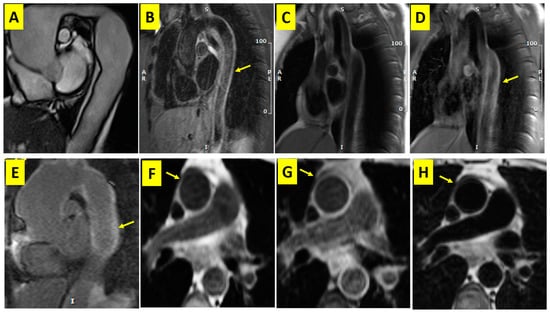

| Presence of Aortic Wall Thickening | Thickened | 37 (100) | Normal | 0 |

| Aortic Mural Edema * at Presentation n (%) | Positive | 34 (92) | Negative | 4 (11) |

| Aortic Hyperenhancement ¥ at Presentation n (%) | Positive | 36 (97.3) | Negative | 1 (2.7) |

| Myocardial Subepicardial and Mid-Wall Fibrosis ¥ at Presentation n (%) | Positive | 6 (16.3) | Negative | 31 (83.7) |

| ACCCMR (%) | DCM | 1 (2.7) | Main PA aneurysm | 1 (2.7) |

| LPA stenosis | 1 (2.7) | Myocarditis | 6 (16.2) | |

| Severe AR | 2 (5.4) | Aortic dissection | 1 (2.7) | |

| Ascending aorta aneurysm | 1 (2.7) | |||